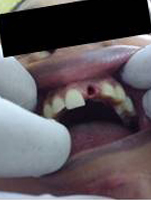

Pre Operation

Use of Bone Graft & GTR membrane for an Implant

Before Placement of Prosthesis

After Placement of Prosthesis